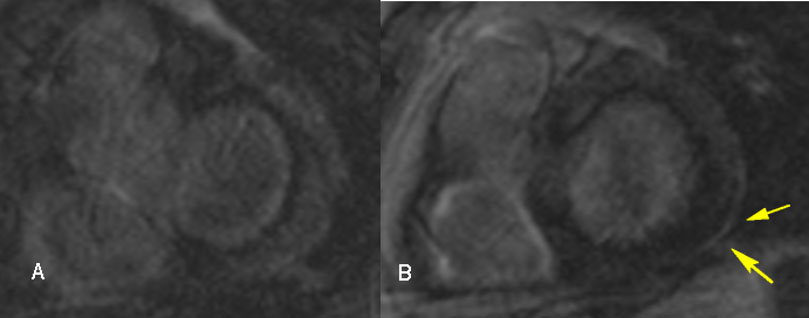

Recent studies have focused on the diagnostic and prognostic value of advanced cardiac imaging, trying to overcome the limitations of the aforementioned exams, in order to achieve an earlier diagnosis, at less advanced stages of the disease (Cheong et al., 2009; Kim et al., 2009; Patel et al., 2009). CMR showing late gadolinium enhancement (LGE) is regarded as the study of choice for diagnosing cardiac involvement in sarcoidosis (Smedema et al., 2005). Apart from LGE, CMR may detect morphologic abnormalities (such as wall thinning and aneurysms) and functional parameters of cardiac chambers (LV and RV). LGE most commonly represents scar tissue, although inflammation may sometimes lead to extracellular expansion leading to LGE. In a study of 321 biopsy-proven sarcoidosis patients, CMR allowed the diagnosis of 44 patients with normal echocardiograms, as well as 15 asymptomatic patients. LGE may independently predict future adverse events, such as atrioventricular block (AVB), ventricular tachycardia (VT), sudden cardiac death (SCD) and heart failure (Nadel et al., 2015). Association of LGE on CMR with adverse cardiac outcomes is shown in other studies as well (Ichinose et al., 2008; Nagai et al., 2014). There is often a multifocal distribution, although a pattern of enhancement is not pathognomonic for CS (Cummings et al., 2009). LGE is mostly seen in basal segments, particularly of the septum and lateral wall, and usually in the midmyocardium and sub-epicardium (non-infarct pattern) as opposed to sub-endocardial scarring in the event of myocardial infarction. Few studies have focused on right ventricular involvement, suggesting that the RV free wall may also be involved in predicting adverse outcomes, particularly ventricular tachyarrhythmias (Crawford et al., 2014; Patel et al., 2011). The presence of LGE in patients with normal or near-normal LVEF greatly increases the likelihood of adverse events (Agoston-Coldea et al., 2016; Coleman et al., 2017; Ekström et al., 2016; Ise et al., 2014; Murtagh et al., 2016; Shafee et al., 2012; Yasuda et al., 2016). Remarkably, CMR identifies small regions of myocardial damage in subjects with preserved LV systolic function, allowing detection of “silent” CS (Pizarro et al., 2016). Interestingly, involvement of the RV in addition to the LV increases the risk of worse outcomes and all-cause mortality (Smedema et al., 2017). CMR with LGE is less sensitive regarding active myocardial inflammation; consequently, it may not properly guide immunosuppressive therapy. Moreover, CMR is not useful for extra-cardiac sarcoidosis compared to CT and PET-CT. Novel CMR techniques utilizing T1 and T2 mapping may allow detection of myocardial inflammation, suggesting a role in monitoring response to treatment (Crouser et al., 2014; Puntmann et al., 2017). The main value of CMR in the diagnostic algorithm of CS is its high negative predictive value, which exceeds 90% (Cheong et al., 2009). Representative CMR images of cardiac sarcoidosis are shown in Fig. 2.

Fig. 2.

Fig. 2.Cardiac magnetic resonance images in a 54-year-old male with cardiac sarcoidosis, showing late gadolinium enhancement in the posterior-lateral left ventricle wall sub-epicardially (B, yellow arrows).